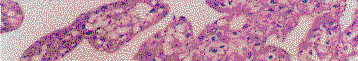

1.HIFU治疗后手术病例效果分析: ①HIFU破坏肿瘤病灶的范围,手术切除肿瘤,立即纵行剖开病灶,肉眼观察HIFU治疗区与非治疗区的组织学变化,发现预定靶区与实际治疗范围完全重合,无1例出现脱靶现象。②HIFU破坏肿瘤的程度,HIFU覆盖区为凝固性坏死,边缘有一充血出血带。受损区域与邻近正常组织分界清楚。③计划治疗范围与实际受损范围基本相等,两者之间差异无统计学意义。④HIFU破坏肿瘤的组织学特征,肉眼观察破坏区为无光泽的凝固性坏死区,肿瘤松散易碎,外面有一充血出血带(图2);光镜检查见肿瘤细胞间隙明显增大,排列稀疏,胞浆嗜红染色增强,核固缩、核溶解现象明显(图3);电镜观察肿瘤细胞结构模糊,质膜、核膜连续性丧失,胞浆内细胞器消失,出现一片电子密度均匀结构或大小不等的泡样结构,核碎裂、核溶解现象明显(图4)。⑤HIFU剂量与效应的关系,在治疗声强和治疗方式一致、剂量分布均匀条件下,破坏的肿瘤体积与实际治疗时间呈正相关关系。

图3 HIFU治疗后肿瘤细胞光镜变化